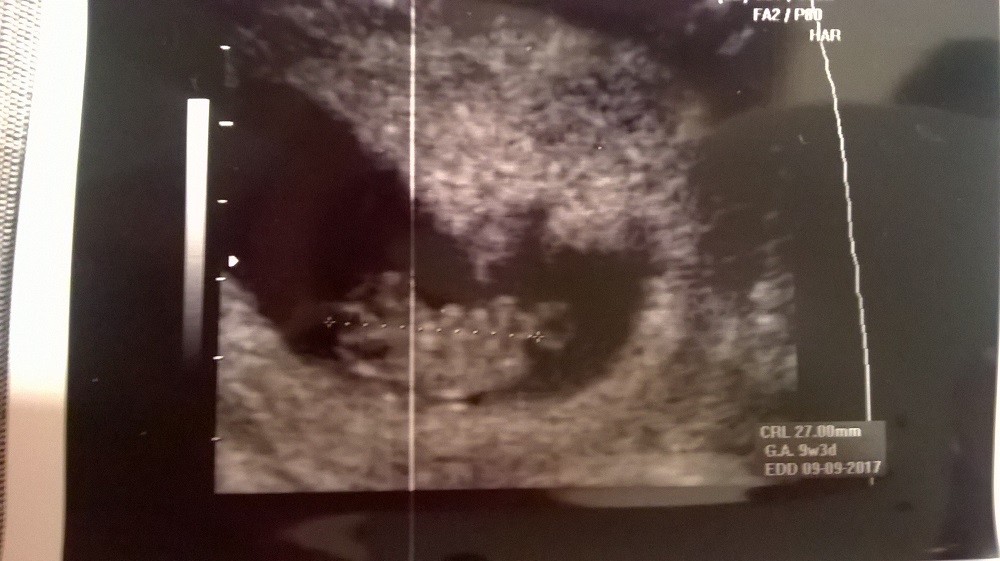

Wrzucę foty ...czekaj :)

Załączniki

• WP_20170207_013.jpg

WP_20170207_013.jpg

171,4 KB · Wyświetleń: 78

• WP_20170207_014.jpg

WP_20170207_014.jpg

163,2 KB · Wyświetleń: 75

• WP_20170207_015.jpg

WP_20170207_015.jpg

174,8 KB · Wyświetleń: 74